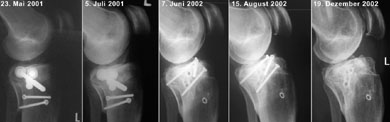

Der Röntgencheck in Chur brachte eine besorgniserregende Erkenntnis: Die Schmerzen am unteren Patellarand könnten von einer bereits beginnenden Arthrose herrühren (siehe weiter unten). Ansonsten hab ich wieder eine Lizenz zum Skifahren - und die Gewissheit, dass ich keine grössere Schwellung mehr im Knie habe. Und immerhin bin ich vom Metall befreit... ausser dem "Heiligenschein" rechts unten, einer eingewachsenen Unterlagsscheibe, die immerhin dereinst Angestellte eines Bestattungsunternehmens beschäftigen wird: "Wie finden wir das kleine Ding, das in dieser Urne so klimpert?" - Die folgende Bilderserie zeigt der Verlauf von den Schrauben der ersten OP über diejenigen der Korrekturosteotomie vom April 2002 bis zum Dezember 2002.

Sie können auf die einzelnen Bildfragmente klicken, um eine grössere Fassung des Ausschnittes zu sehen.

Sorgen macht die Kniescheibe: Auf der folgenden Bilderserie von Mai 2001 bis Dezember 2002 (aufs Bild klicken für Originalgrösse!) ist deutlich sichtbar, wie sich am linken unteren Patellarand ein kleiner Höcker gegen das Wadenbein hin bildet. Dieser Auswuchs (Osteophyt) könnte der Grund für den noch vorhandenen Hauptschmerz sein; er könnte auch vom Bechterew herrühren oder durch diese Krankheit zumindest verstärkt worden sein.

Ebenfalls gut zu sehen ist jedoch die schöne Heilung der ursprünglichen Bruchstelle (links unten im Bild) - einen Monat nach der Operation (links) klafft noch eine deutliche Lücke, die im Lauf der Zeit von neuer Knochenstruktur überwachsen wird.